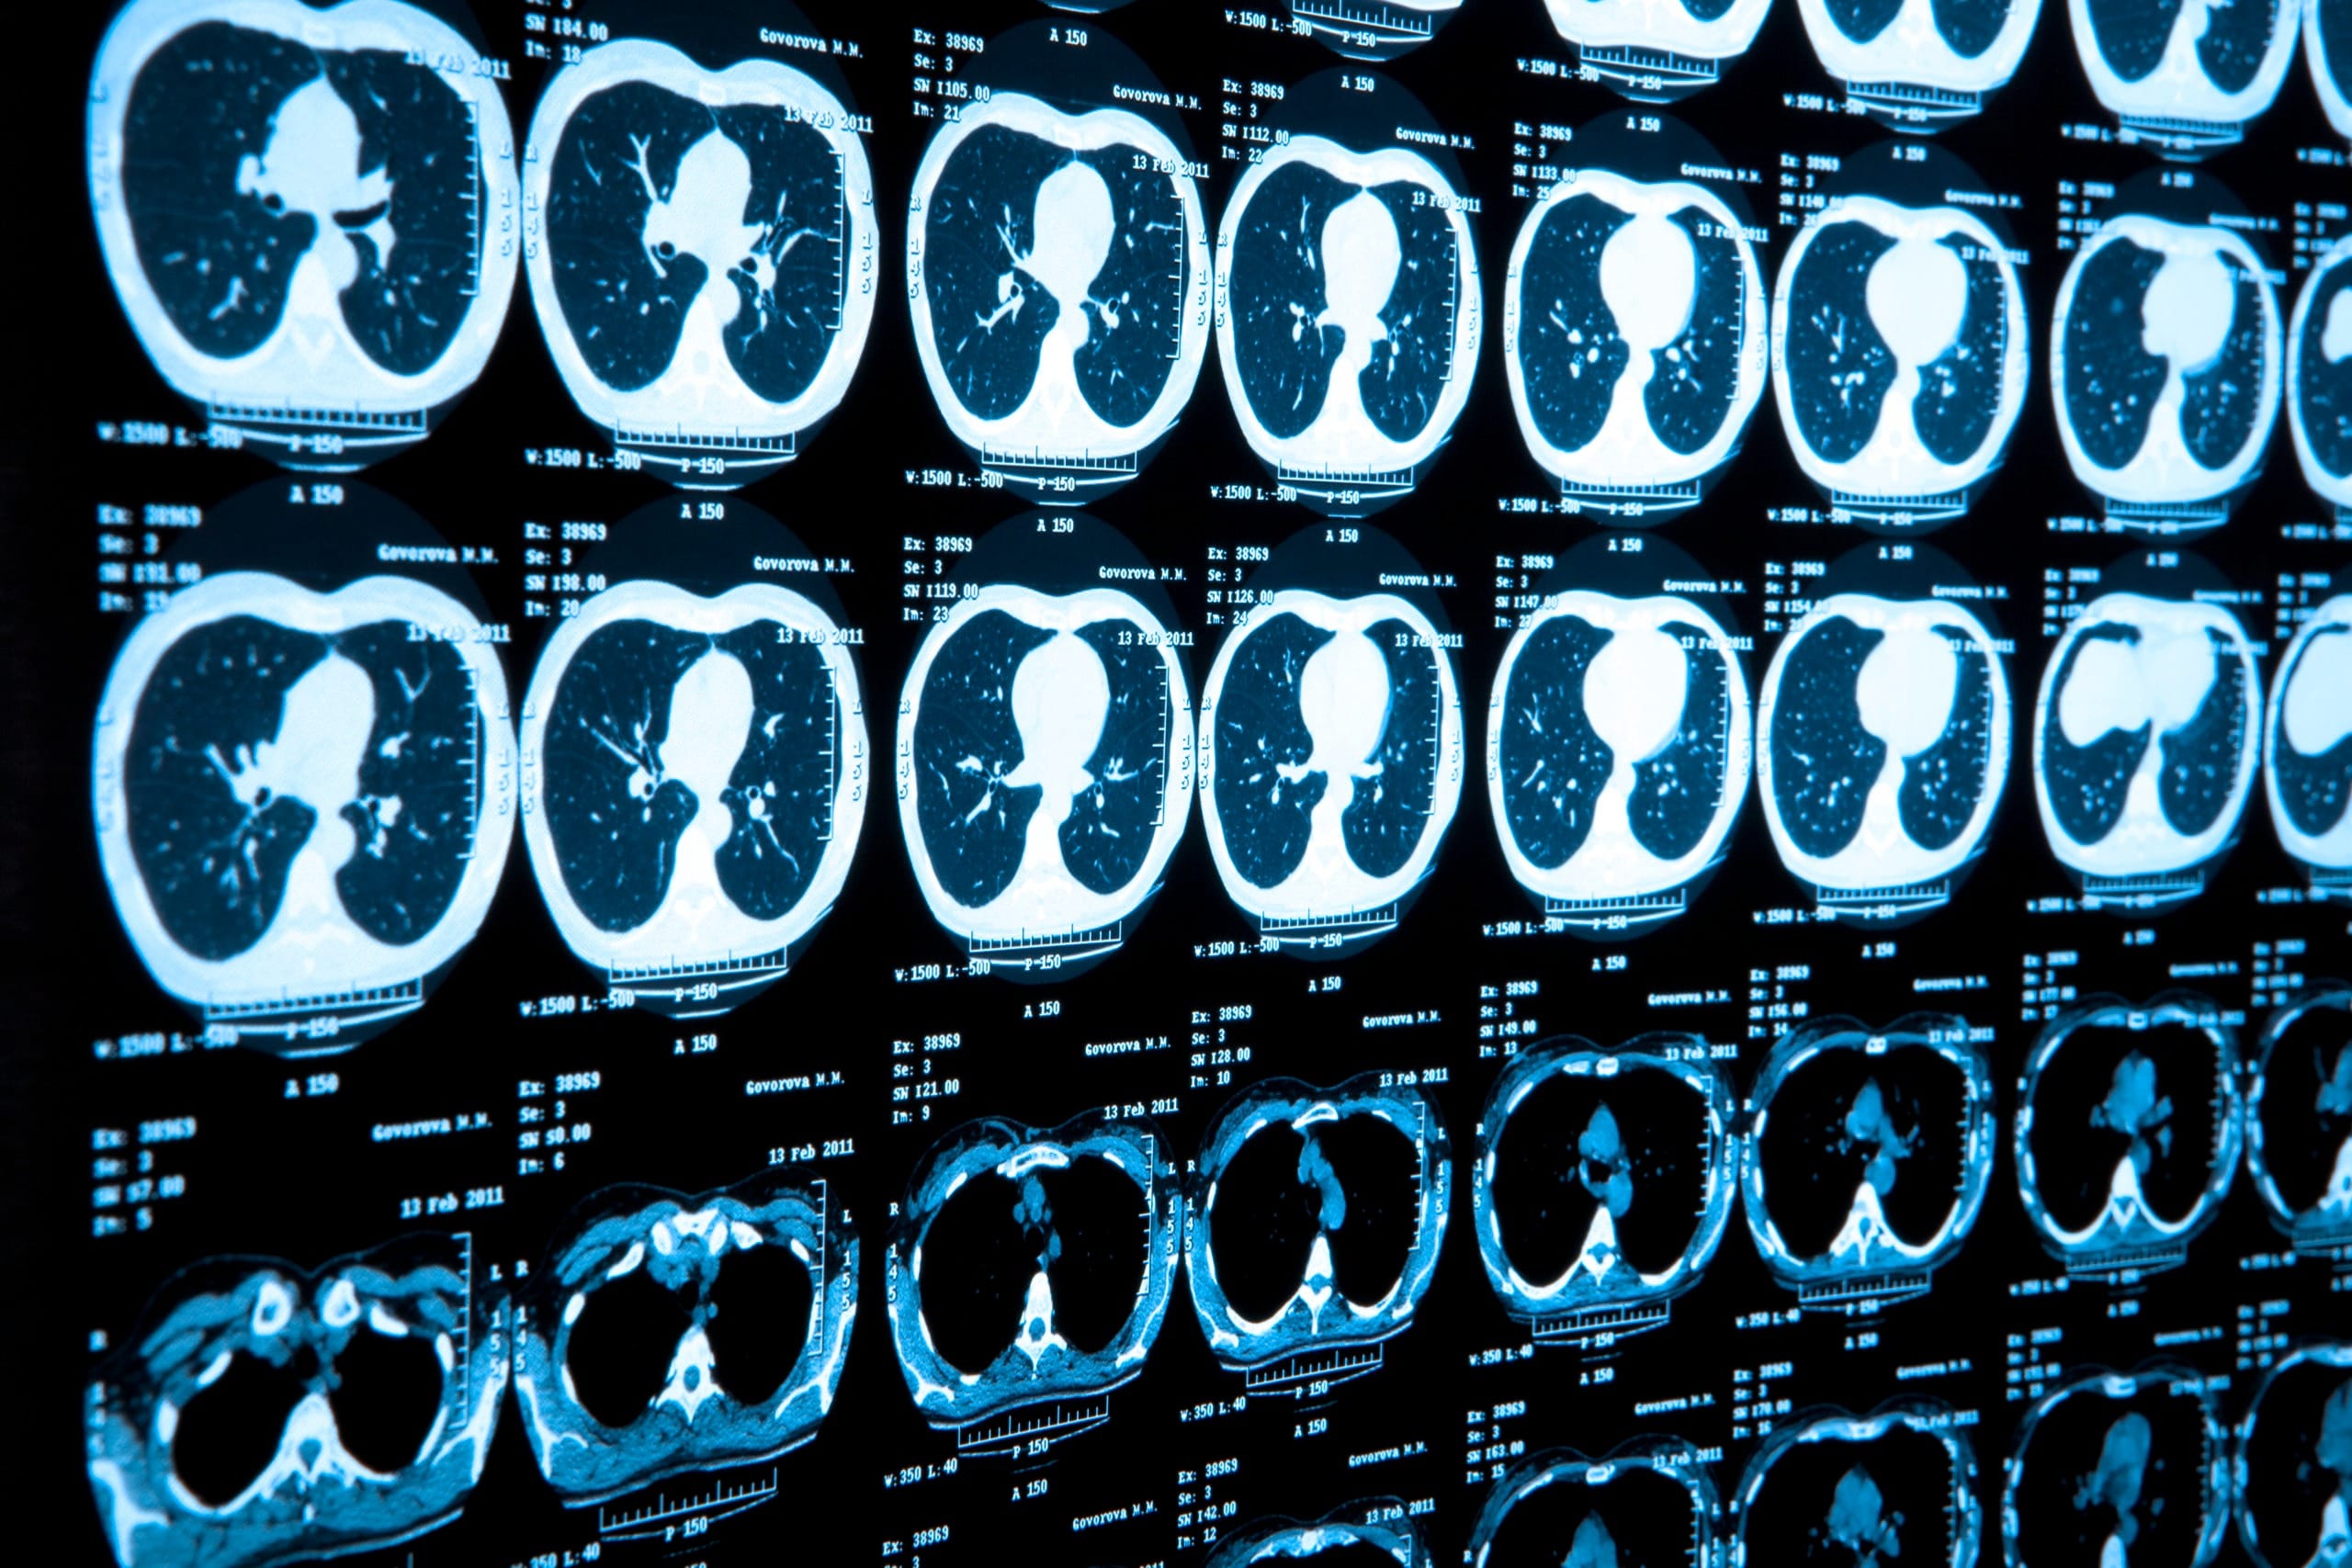

Low-Dose CT for Lung Cancer

What it is: A specialized CT scan used to screen for lung cancer in high-risk individuals, such as smokers.

Who it’s for: Current and former heavy smokers aged 50-80.

Why it matters: Early detection of lung cancer can more than double survival rates.

- AI-Driven Diagnostics that analyze imaging results faster and more accurately.